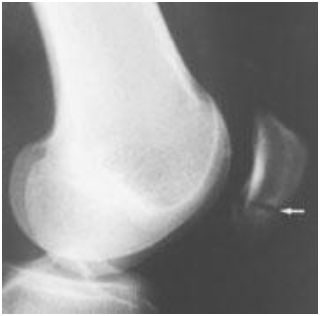

Radiografi adalah modalitas utama untuk mengidentifikasi fraktur yang jelas pada femur distal, plateau tibia, dan patela. Meskipun hanya 5% radiografi lutut di UGD yang menunjukkan fraktur, 86% dari semua fraktur lutut disebabkan oleh trauma tumpul, yang menggarisbawahi pentingnya radiografi ketika mekanisme dan tanda-tanda klinisnya sesuai.

Gambar 1. Fraktur pada pole bawah patella